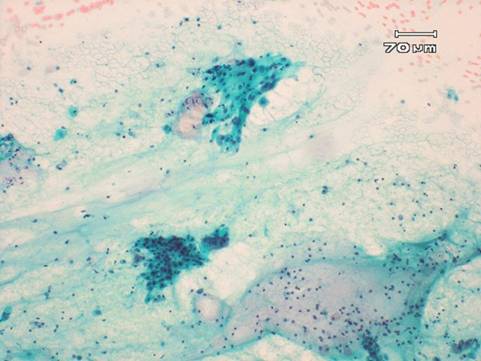

細胞診所見

炎症性変化は少なく、萎縮性変化を示す細胞が主体で、一部にクロマチンの軽度増量した異型扁平上皮細胞を認めた。

また不規則な重積性があり、細胞質はやや厚く、核の大小不同、核異型、クロマチンの増量した異型腺細胞を、乳頭状に認めた。

細胞診では疑陽性とした。